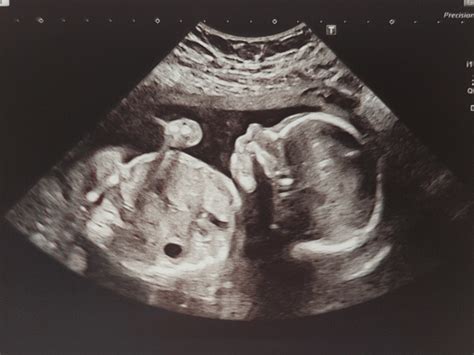

\The 20-week anatomy scan is a detailed ultrasound that checks your baby’s development. It’s a crucial appointment where sonographers and doctors look at everything from the baby’s heart and brain to their limbs and organs. Most of the time, everything looks great, and it’s a joyous occasion. However, sometimes the scan reveals potential issues, which can be incredibly stressful for expectant parents. Finding out something might be wrong is undoubtedly scary, and it’s normal to feel anxious, confused, or even overwhelmed. One of the first things to remember is that the ultrasound is just a screening tool. It provides a picture, but it’s not always a definitive diagnosis. Further tests, like additional ultrasounds, amniocentesis, or other specialized screenings, might be necessary to get a clearer understanding of the situation. It’s also super important to lean on your healthcare provider for guidance. They can explain the findings in detail, discuss potential implications, and outline the next steps. Don’t hesitate to ask questions – no question is too silly or insignificant when it comes to your baby’s health. Connecting with other parents who have gone through similar experiences can also be immensely helpful. Online forums, support groups, and communities (like those on Reddit) offer a space to share your feelings, learn from others, and find emotional support. Remember, you’re not alone, and there are people who understand what you’re going through. Staying informed is key, but be cautious about relying solely on the internet. While online research can be helpful, it’s crucial to verify information with your healthcare provider and avoid self-diagnosing. Every pregnancy and every baby is unique, so what you read online might not apply to your specific situation. Focus on gathering accurate information from reliable sources and working closely with your medical team to make informed decisions.

So, what kind of findings might raise concerns at a 20-week scan ? There’s a range of possibilities, some more serious than others. Soft markers, such as an echogenic bowel or a choroid plexus cyst, are often detected. These markers, while sometimes associated with chromosomal abnormalities, frequently resolve on their own and don’t indicate a serious problem. However, doctors typically recommend further testing, like a non-invasive prenatal test (NIPT) or amniocentesis, to rule out any underlying issues. Structural abnormalities, such as heart defects, kidney problems, or neural tube defects, are more significant findings. These conditions require careful evaluation and planning. Depending on the severity, interventions might range from monitoring during pregnancy to surgery after birth. In some cases, the scan might reveal issues with the placenta or amniotic fluid levels. These conditions can affect the baby’s growth and development and may require frequent monitoring and potential interventions to ensure the baby’s well-being. When a potential issue is identified, doctors will typically order follow-up tests to confirm the diagnosis and assess the severity. These tests might include a more detailed ultrasound, fetal echocardiogram (for heart issues), or amniocentesis to analyze the baby’s chromosomes. It’s essential to understand the purpose of each test and what the results might reveal. Remember to discuss any concerns or questions you have with your healthcare provider. Depending on the diagnosis, a specialist might be involved in your care. For example, if a heart defect is suspected, a pediatric cardiologist will be consulted. A multidisciplinary team can provide comprehensive care and support throughout your pregnancy and after the baby is born. Knowing what to expect and having a plan in place can help alleviate some of the anxiety associated with unexpected findings. While it’s impossible to eliminate all worries, being proactive and informed can empower you to make the best decisions for your baby and yourself.